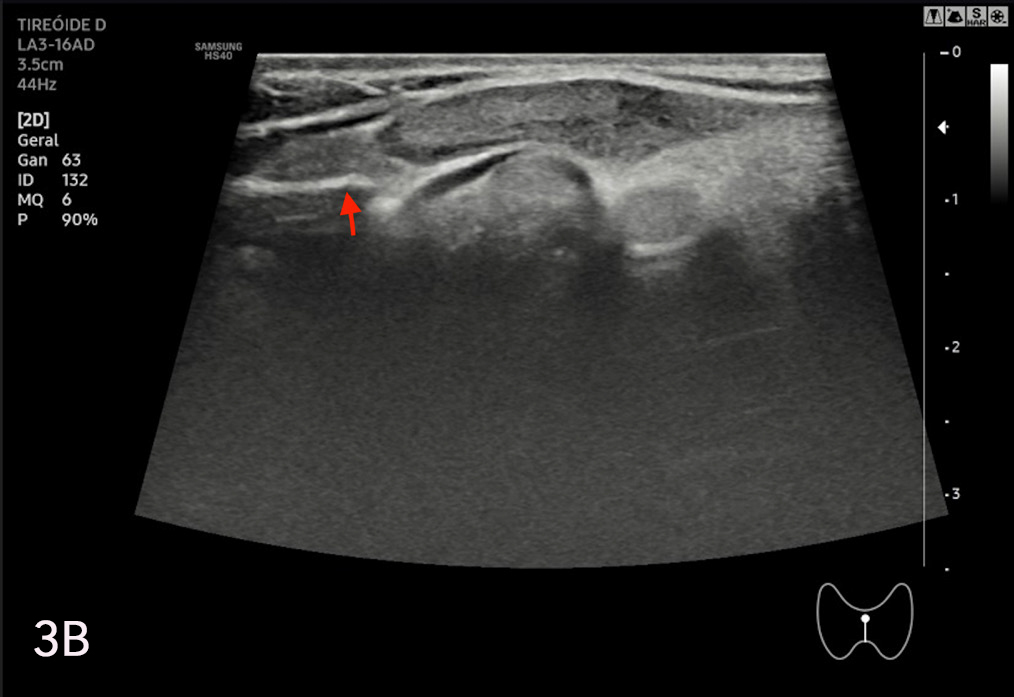

La eco estructura es homogénea, los márgenes son regulares y presenta una cápsula ecogénica, su vascularización es escasa. El rango de referencia para una tiroides normal es de entre cinco y diez vasos visibles dentro de la exploración de cada lóbulo valorado con Doppler color2. Se ha descripto que hasta un 50% de los individuos presentan lóbulo piramidal (Figura 3a y 3b). Este sector, en general, es similar en ecogenicidad, homogeneidad y vascularización al istmo y los lóbulos. En la superficie posterior de los lóbulos tiroideos, especialmente en el segmento inferior, puede visualizarse el tubérculo de Zuckerkandl, un ejemplo de este se puede observar en la figura 4a y 4b. Este es un tabique hiperecogénico fibroso que a menudo genera sombra posterior. Se forma por la extensión del tejido tiroideo de las áreas laterales de los lóbulos hacia el sector posterior, y a menudo exhibe una disminución de la ecogenicidad detrás del mismo. Este proceso puede imitar una lesión tiroidea o paratiroidea y causar dificultades en la interpretación2.

Figura 2: Corte transversal de la tiroides normal, se señalan con las

flechas distintas estructuras.